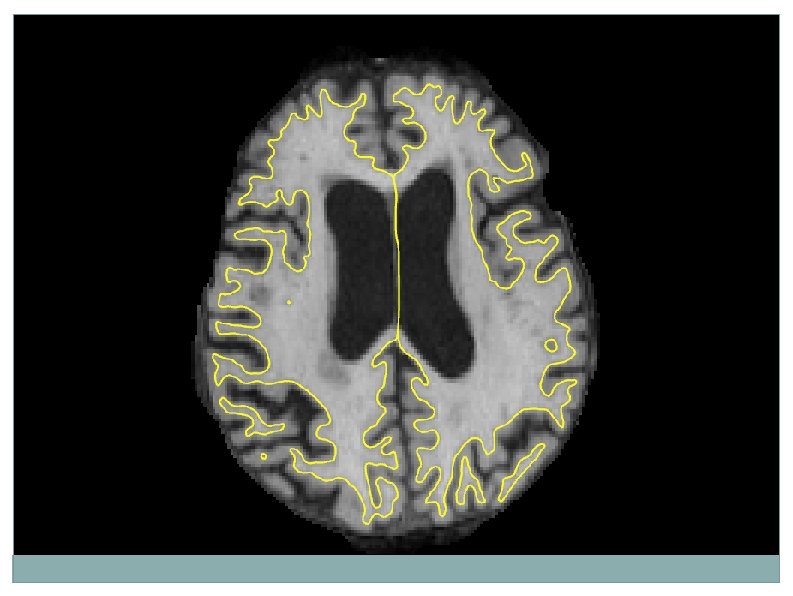

Robust Unbiased Subject Template 1. Create subject template (iterative registration to median) 2. Process template 3. Transfer to time points 4. Let it evolve there - All time points are treated the same - Minimize overregularization by letting tps evolve freely Reuter et al. OHBM 2010, Neuro. Image 2011 & 2012

Test-Retest Reliability Subcortical Cortical [LONG] significantly improves reliability 115 subjects, MEMPRAGE, 2 scans, same session Reuter et al. Neuro. Image 2012

Test-Retest Reliability Diff. ([CROSS]-[LONG]) of Abs. Thick. Change: Significance Map [LONG] significantly improves reliability 115 subjects, ME MPRAGE, 2 scans, same session Reuter et al. Neuro. Image 2012